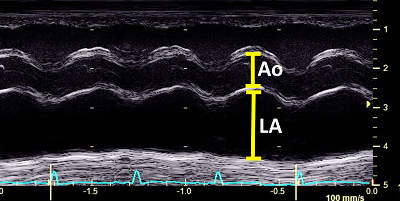

One of the primary calculations which veterinary cardiologists make when gathering data during echocardiographic (echo) scans of dogs' hearts is the LA/Ao ratio (LA ÷ Ao). "LA" stands for the left atrium of the heart, and in this context it is the linear diameter of the left atrium in either millimeters (mm.) or centimeters (cm.). "Ao" stands for the aortic root of the heart, and that is the linear diameter of the aorta artery at its starting point in the left ventricle of the heart, similarly in millimeters or centimeters.

A dilemma which veterinary cardiologists face when performing an initial echo scan of the heart of a MVD-affected dog is how to determine upon that initial scan whether the LA still is of normal size or already has begun to enlarge. Researchers attempt to resolve that difficulty by predicting the size of normal-sized LAs. The LA/Ao ratio was devised by medical researchers in a 1974 study of humans, based upon the assumption that humans' normal sized LAs and Aos are proportional to each other, and so the LA/Ao ratio can indicate a reference range of normal sized human left atriums and degrees of left atrial enlargement. If a patient's heart had never been echo scanned prior to suspected left atrial enlargement, the LA/Ao reference range can be used as a best guess as to whether any enlargement already has occurred.

That said, the LA/Ao clearly has no useful role whatsoever when examining only a single dog's heart to determine if that dog's LA has enlarged between two consecutive echo exams. Since the Ao's diameter can be different in different echo scans of the same dog, when the Ao is included in an effort to determine if only the LA has increased in size, the result completely falsifies the diagnosis. Only if the Ao diameter is constant for all echo scans of that dog -- a very unlikely event -- will the LA/Ao ratio provide any useful information about the size of the dog's LA.

Consider this example: A cavalier King Charles spaniel, already diagnosed

with MVD, has an initial echocardiogram in 2025 showing the LA dimension of

26 mm. and the Ao dimension of 15 mm., resulting in a LA/Ao ratio of 1.73.

An LA/Ao of that size in most cavaliers would indicate that the left atrium

was somewhat enlarged, since normal sized left atriums of cavaliers have a

LA/Ao range from 0.47 to 1.36. So, the cardiologist probably correctly

decides that the LA is enlarged, due to the MVD. On a scale of

"mild/moderate/severe", he categorizes the enlargement as "mild", since he

follows the

ACVIM's 2019 Consensus Statement's erroneous, species-wide definition of

left atrium enlargement as having a LA/Ao of at least 1.6. He prescribes a

starting dosage of pimobendan. He recommends a follow-up echo in 9 to 12

months.

Nine months later in 2026, the same cardiologist, using the same ultrasound equipment, performs a second echocardiogram on the cavalier, in which the LA dimension is 26 mm. (same as the first one) and the Ao dimension is 13 mm. (2 mm. less than the first one), resulting in a LA/Ao ratio of 2.00. The intellectually lazy cardiologist notes that this second LA/Ao, being higher than the first one nine months previously, indicates that the left atrium has continued to enlarge, and that the degree of enlargement now is "moderate-to-severe". He increases the dosage of pimobendan.

The cardiologist ignored the two measurements of just the LA and focused only upon the differences in the LA/Ao ratios in 2025 and 2026. Inarguably, if the question is whether the LA has enlarged since nine months ago, would not comparing only the two measurements of that LA alone give the answer? Obviously, yes!

In this 2002 seminal veterinary journal article on the use of the LA/Ao in detecting left atrial enlargement -- Left atrial to aortic root indices using two-dimensional and m-mode echocardiography in cavalier king charles spaniels with and without left atrial enlargement -- authors Kerstin Hansson, Jens Haggstrom, Clarence Kvart, and Peter Lord warned against blindly relying upon the LA/Ao as the ultimate determinant of LA enlargement. They stated:

"If the Ao dimension becomes increased or decreased, it would alter the resulting ratio and give an under- or over-estimation of LA size. In such instances, an LA/Ao index, whether it is M-mode or two-dimensionally (2-D) derived, needs to be used with caution and only as a guideline." (p. 569)